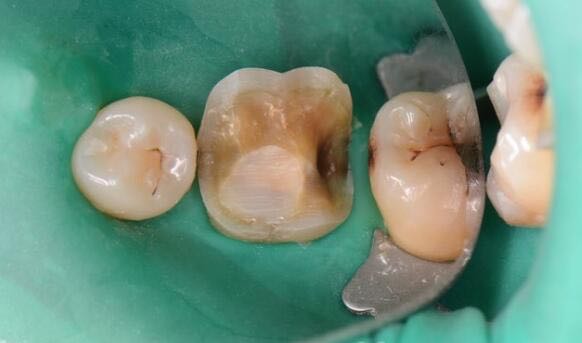

患者女性,自诉左下后牙咀嚼不适一个多月,食物嵌塞,来诊求治

检查:36远中临合洞,he面银汞充填物,X光见髓腔内有高密度影像,干髓术后,根尖无骨密度减低区

36牙中龋 36牙嵌体修复